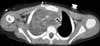

DISCUSSION: In addition to the lateral neck mass, physicians in the emergency department noted dilated superficial vessels on the right anterior chest wall (Figure 1). A chest radiograph demonstrated a large density in the right upper lobe with a mediastinal shift to the left side (Figure 2).